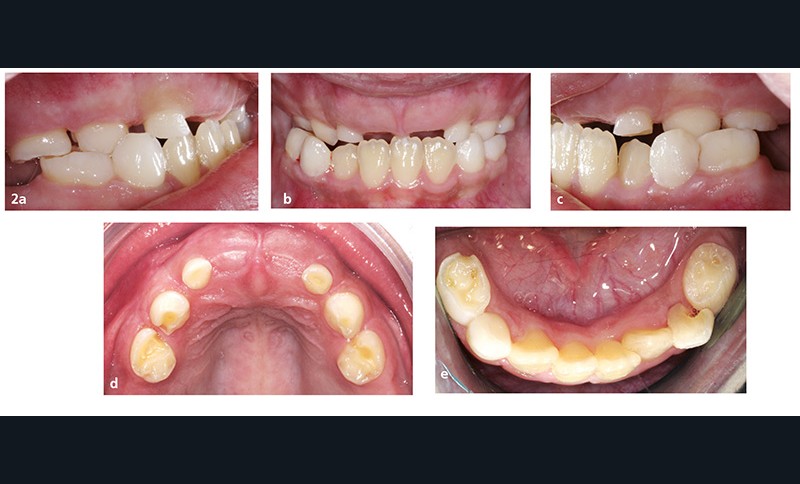

L’examen endo-buccal (fig. 2a à e) montre, au maxillaire, la présence des incisives latérales, canines et premières molaires temporaires (les incisives centrales étant tombées depuis la réalisation de la radiographie panoramique) et l’absence de toutes les dents permanentes et des deuxièmes molaires temporaires. À la mandibule, les quatre incisives permanentes ont évolué et il persiste les canines et les premières molaires temporaires. Aucune autre dent n’est visible dans la cavité buccale.

Les relations occlusales sagittales sont subnormales, mais on constate une insuffisance transversale de l’arcade maxillaire…